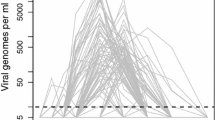

Measles infection dose responses: insights from mathematical modeling. Top: Model-data fits for acute viremia in response to changes in measles infection doses. \(10^4\), \(10^3\), \(10^2\), 10 and 1 TCID\(_{50}\) correspond to red diamonds, blue stars, orange triangles, magenta dots, and green squares respectively. The solid lines represent the trajectories generated by the proposed model parameterization. The shapes represent data. The dark grey dotted dashed line represents the limit of detection < 0.3. Bottom: Cartoon illustrating that when the measles infection dose increases, the stimulation of the measles-specific cellular immune responses increases early on post-infection. This enhanced immune response reduces the time required to clear the infectious viral load and helps maintain similar levels of viral loads and lymphocyte depletion irrespective of the initial dose.

Measles infection dose responses: insights from mathematical modeling. Top: Model-data fits for acute viremia in response to changes in measles infection doses. \(10^4\), \(10^3\), \(10^2\), 10 and 1 TCID\(_{50}\) correspond to red diamonds, blue stars, orange triangles, magenta dots, and green squares respectively. The solid lines represent the trajectories generated by the proposed model parameterization. The shapes represent data. The dark grey dotted dashed line represents the limit of detection < 0.3. Bottom: Cartoon illustrating that when the measles infection dose increases, the stimulation of the measles-specific cellular immune responses increases early on post-infection. This enhanced immune response reduces the time required to clear the infectious viral load and helps maintain similar levels of viral loads and lymphocyte depletion irrespective of the initial dose.

In contrast, when MV infection doses are \( \ge 1\) TCID\(_{50}\), viremia increases up to a peak before decreasing to undetectable levels (Fig. 1a), suggesting a threshold or stochastic processes by which low numbers of infectious MV particles facilitate the establishment and transmission of MV infection (Norrby 1985; Laksono et al. 2016). Since the viremia remains below the limit of detection in the peripheral blood for at least the first 3 days post-infection for all infection doses, this suggest that infectious MV particles are lost in large numbers during intratracheal infection, or absent in the peripheral blood likely due to intracellular delays, slow transfer from the respiratory route, and MV sequestration in lymphoid tissues (Lemon et al. 2011; Griffin 2020); alternatively, infectious MV particles could be present in small numbers, and increasing or fluctuating in PBMCs below the limit of detection, as observed for HIV dynamics (Fiebig et al. 2005; Kahn and Walker 1998).

When MV infection dose increases for \( \ge 1\) TCID\(_{50}\), we observe synchronisation between MV growth and immune control, since the day of the first detectable viremia and to the day of peak viremia decrease nonlinearly in identical quantities i.e. \(-4\) days from 1 TCID\(_{50}\) to \( 10 \le TCID_{50} \le 10^3\), and \(-2\) days from \(10^3\) to \(10^4\) TCID\(_{50}\) (Fig. 1), suggesting dose-dependent virus-host interactions in the blood and tissues while viremia is still undetectable during the early days post infection, and this is in agreement with epidemiological findings where high MV exposure is associated with short MV incubation period, early rash mediated by early cellular immunity (Aaby 1992, 1995, 1991). When MV infection dose increases for \( \ge 1\) TCID\(_{50}\), the peak viremia remains almost constant at about 3.3 \(TCID_{50}\) per \(10^6\) PBMCs, supporting the notion that cellular immunity plays the role of a predictable and robust control mechanism to achieve clearance of acute viremia (Anelone et al. 2021) (see Fig. 1a, b).

When acute viremia is above the limit of detection i.e.\( \le 0.3\) \(log_{10} TCID_{50}\) per \(10^6\) PBMCs, acute viremia increases and decreases almost linearly on the log scale, with almost symmetrical slopes for the growth and decline, and almost the same slopes for different infection doses. Consequently, we performed linear regressions and estimated the corresponding viral growth rate, \(r_d = 0.56\) \( LogTCID_{50}/10^6\) PBMCs per day, \(p<0.001\), and decline rate, \(\delta _d = -0.48\) \( LogTCID_{50}/10^6\) PBMCs per day, \(p<0.001\), irrespective of MV infection doses. This suggests that when viremia is above the limit of detection, MV growth and clearance are independent of the antigen stimulation induced by MV infection doses (see Fig. 1b). Consequently, MV infection doses \( \le 10^4 \) and \( \ge 1\) TCID\(_{50}\) lead to similar duration for detectable viremia, approximately 8 to 9 days (Fig. 1b), and similar area under the curve (AUC) for acute viremia, \(AUC= 4.598\) on average, suggesting similar MV exposure and effects in the peripheral blood irrespective of the infection doses. Together, these salient features of MV infection dose responses suggest that measles exhibits dose-dependent virus dynamics in the early days post infection, followed by dose independent viral growth, where the peak viremia and viral clearance are predictably regulated by consistent adaptive immune responses. Thus, these findings also motivate additional studies on early measles dynamics.

Salient features of MV infection dose responses. a Time course of PBMC-associated acute viremia following wild type measles infection of cynomolgus monkeys with different doses. The different colours and points represent different TCID\(_{50}\) for infection. The dark grey dotted dashed line represents the limit of detection \(< 0.3\). Data from (van Binnendijk et al. 1994). b MV infection dose responses where the peaks of viremia are aligned. Each black tick corresponds to a day on the x-axis. The oblique block line is the linear regression to estimate the growth rate \(r_d = 0.56\) \( LogTCID_{50}/10^6\) PBMCs per day, \(S.D. = 0.03 \), \(p<0.001\) with intercept \(-1.69\) \(LogTCID_{50}/10^6\) PBMCs, \(S.D.= 0.23\), \(p<0.001\). We considered significance levels with a p-values \(<0.05\). The oblique dashed block line is the linear regression for the decline rate \(\delta _d = -0.48 \) \(LogTCID_{50}/10^6\) PBMCs per day, \(S.D. = 0.06 \), \(p<0.001\), with intercept 9.77 \(LogTCID_{50}/10^6\) PBMCs, \(S.D.= 0.79\), \(p<0.001\)